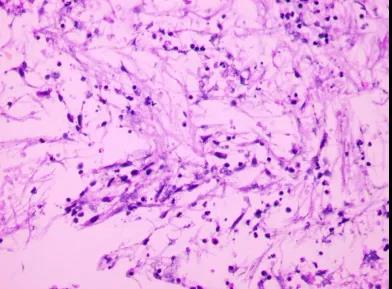

4月14日更改治疗方案:伏立康唑针400 mg静滴q12h。患者有谵妄发作,考虑药物副反应可能,4月15日改为两性霉素B脂质体,首次10 mg静滴,后逐渐加量至40 mg/d维持治疗。4月28日考虑患者脑室外引流管留置时间已半月,神经外科再次行“脑室镜辅助下右侧侧脑室透明隔造瘘术+左侧ommaya囊置入术”。术中见脑室内脑脊液浑浊,脑室壁附着较多絮状物、孟氏孔被絮状物堵塞。先钳取脑室壁及孟氏孔絮状物,见孟氏孔通畅。再电凝透明隔后造瘘,可见脑脊液引流。术后继续行ommya囊穿刺引流,保持脑脊液引流通畅。脑脊液生化提示“葡萄糖0.01mg/L“。5月1日患者出现左侧瞳孔散大,急查头颅CT检查提示:左侧大脑半球(左侧大脑中、后动脉供血区)梗死(图15)。

图15. 5月1日头颅CT